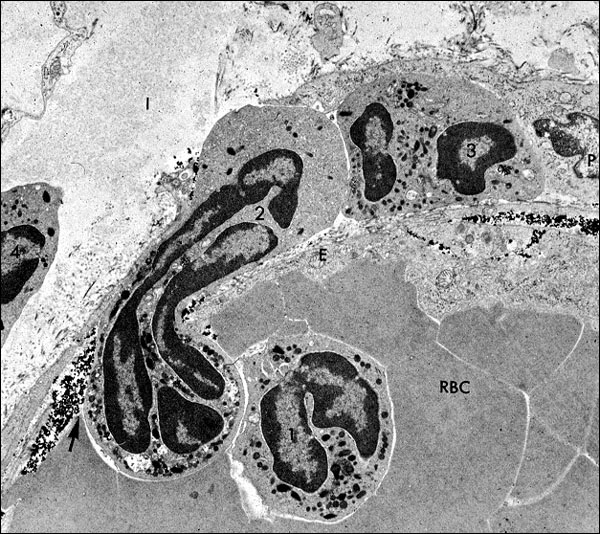

This is an electronmicrograph of a neutrophil caught in the act of exiting a vessel. This process is dependent on the leukocyte locally breaking down the vessel's basement membrane, by directed secretion of hydrolytic enzymes onto the surface of the BM. Erythrocytes in the vessel's lumen are labeled, "RBC", and endothelial cytoplasm that lines the vessel on either side of the emerging neutrophil is labeled, "E". A neutrophil, labeled "1", is still in the lumen. The emerging neutrophil is labeled "2"; one that has reached the outer limits of the vessel wall is labeled "3", next to a pericyte (P) at the right edge of the frame; and one that is free in the extravascular space is labeled "4", at the left edge of the micrograph. Carbon particles are present in the wall of the vessel, under the endothelium, giving proof that this postcapillary venule was in a state of increased permeability (due to endothelial cell contraction caused by inflammatory mediators, like histamine).